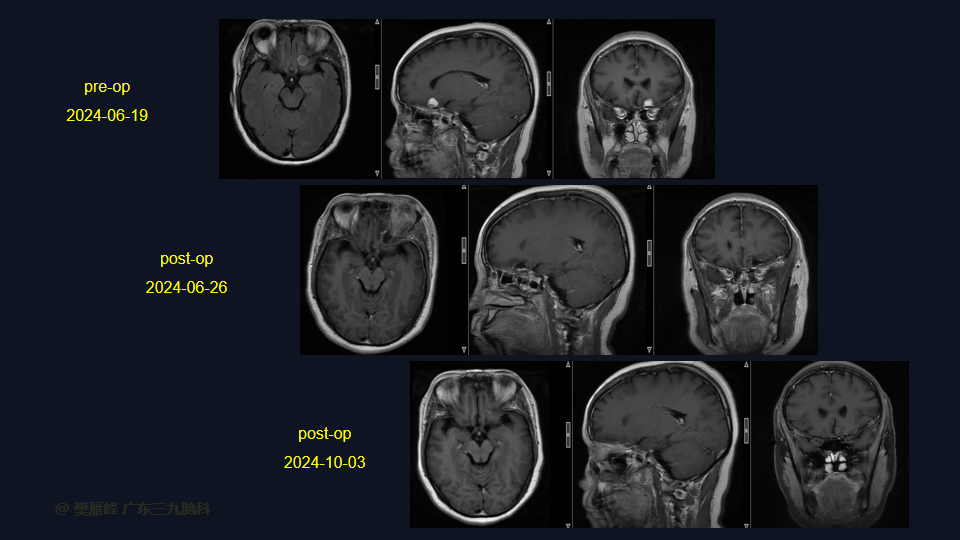

在这个二维手术视频中,展示了一种内镜经眶上锁孔入路微创切除嗅沟脑膜瘤的方法。患者是一名46岁的女性,有2年的头痛病史,近1周出现视物模糊,神经影像学显示左侧前颅窝底部示范围约12×16×10mm的均匀强化的嗅沟脑膜瘤。多种治疗方案被考虑,包括继续观察,开颅切除和内镜下经鼻切除。对于这种情况,内镜下经眶上锁孔切除是理想的治疗选择,因为这种方法避免了需要的脑牵拉,有更高的机会为 Simpson Grade I切除。他接受了内镜下经眉弓锁孔入路保护嗅神经的方法,以实现肿瘤全切除。术后无嗅觉障碍,视力较术前好转,神经影像学显示肿瘤全部切除。我们展示了安全的颅神经保护和内镜下肿瘤切除术的细微差别和技术要点,以及手术技术,以留下最少的残余粘附肿瘤。

在这段手术视频中,展示了一名46岁女性的病例,他因头痛1年余,加重伴视物模糊1周发现的前颅窝底嗅沟脑膜瘤